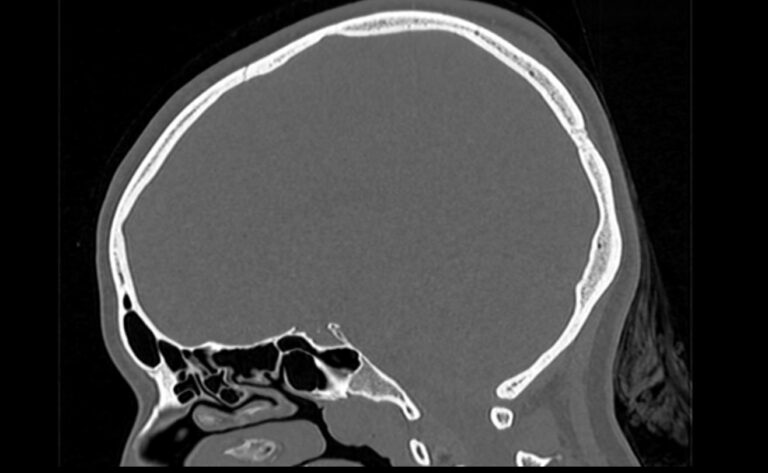

Мультиспиральная компьютерная томография является наилучшим методом диагностики патологии костей черепа. В основе методики лежит использование рентгеновского излучения с последующей цифровой обработкой полученных данных и получения трехмерных реконструкций изображений.

Костная ткань отличается высокой плотностью и способна в большой степени поглощать рентгеновские лучи. Поэтому на послойных снимках, полученных при проведении мультиспиральной КТ черепа можно детально рассмотреть свод черепа, кости лица, основание черепа. Это позволяет с наибольшей точностью визуализировать различные объемные образования, такие как остеомы, дифференцировать фиброзную дисплазию или костные метастазы. Преимуществами методики КТ является отличная визуализация костных структур, быстрота выполнения процедуры и доступная цена. Все это делает КТ незаменимой при диагностике травматических повреждений (например переломов основания черепа или орбит), аномалий развития, при планировании оперативных вмешательств.

Что показывает КТ черепа

- наличие чужеродных предметов;

- скрытые переломы;

- смещение костей;

- опухоли как доброкачественные, так и злокачественные

- нарушенное кровообращение;

- воспалительные заболевания

- метастазы и их локализацию